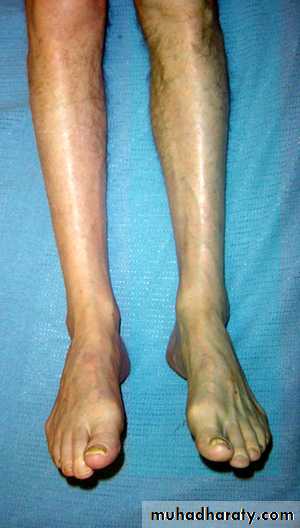

Phlegmasia alba dolens